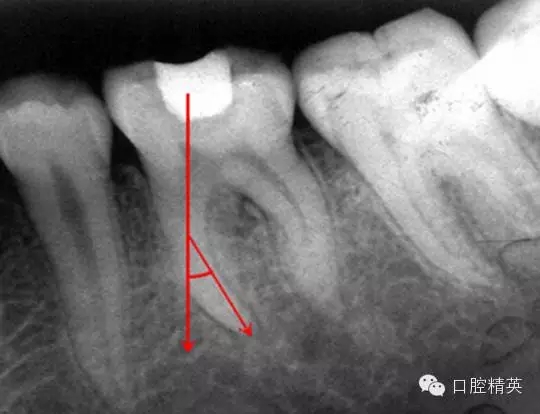

在根管治療的幾年經(jīng)驗中,有些感悟愿與朋友們分享,不到的地方請同仁指正。在做好根管治療時我們首先要攝片分析根管難度選擇合適器具合適方法進行治療,根管難度評估:簡單根管(5-10度)

,中等難度根管,(10-25度)復(fù)雜難度根管(大于25度)

3復(fù)雜根管